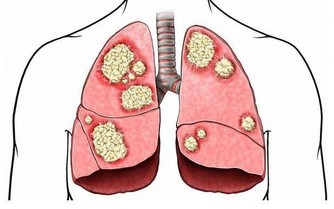

後來患者用了最基本的治療方法,先用碘伏(不是酒精,酒精過於刺激)消毒,由內向外消毒三遍,然後敷上紅黴素軟膏,最後外麵包上乾淨的醫用紗布,一天換藥一次,剛開始流膿比較重的時候,可以一天換藥兩次,保持創面的清潔,一般在第二天的時候,就可以收口,等到一周左右就可以慢慢出現癒合的跡象。同時在治療傷口破潰的時候還要積極的控制住患者的血糖,避免血糖過高影響療效。

最後總結一下3個關鍵點:

1、希望大眾對於糖尿病患者的皮膚傷口引起重視,一旦有糖尿病的患者出現了傷口,就要及時做好消毒工作,防止出現感染。

2、患者傷口如果出現了感染不愈,最好是選擇正規的醫療機構,千萬不要相信偏方,因為這個時候若是不把握住治療的良機,很容易變得更加嚴重。

3、針對傷口,消毒,保持清潔,並且外敷紗布以幫助傷口收澀,這個很重要。最後也是最重要的一點就是控制住自己的血糖情況,才是避免發生皮膚潰爛的關鍵。